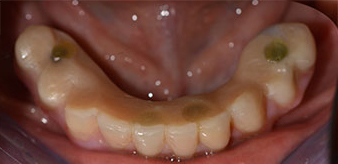

The 64-year-old patient presented with residual dentition of teeth 38, 33 and 43 and a clasp denture in the mandible (Fig. 1 and 2).

residual dentition

Fig. 2